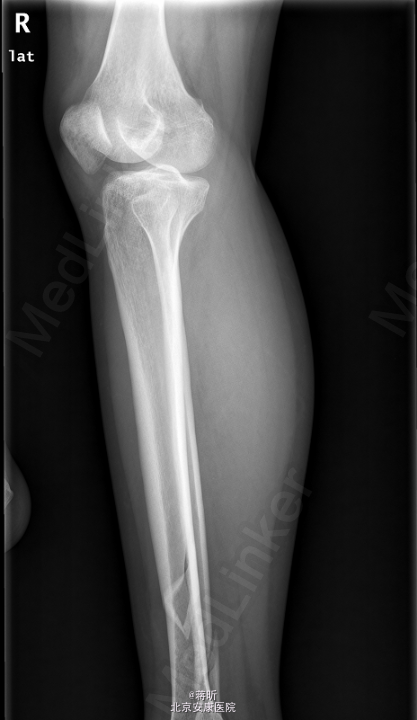

患者,女,32岁,因“右侧胫腓骨骨折术后1月余,发现下肢窦道1周”入院。 患者1月余前因外伤致右侧胫腓骨骨折,于2015-03-24在我院行“右胫骨骨折闭合复位内固定术+右腓骨骨折切复内固术”,术程顺利,术后恢复可,常规拍片复查,1周前自检发现右下肢膝关节处及外踝处出现窦道,伴流脓,无下肢麻木,无感觉异常,无发热寒战等其他不适,患者遂来我院就诊,门诊拟“骨折术后感染收住入院”。既往有“1型糖尿病”病史8年。

右小腿皮温稍高,右膝关节及踝关节活动未受限,右膝及右外踝处可见2处手术疤痕,分别长约7cm及5cm,愈合尚可,右膝正中及右外踝可见3处窦道,可见脓液流出,右足背动脉搏动可及,末梢各趾血循、感觉、活动正常。余肢体无殊。 2015-4-27我院拍片示:右胫骨中下段骨折术后复查。